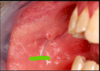

Which systemic disease manifests like this?

Crohn Disease

- Patients can also get angular cheilitis

- Above the Linear ulceration, can see a flap like structure which is the hyperplastic margin